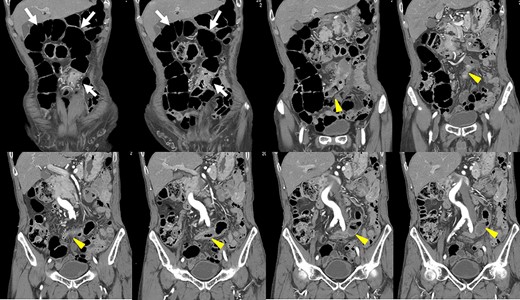

Preoperative computed tomography (CT) revealed a tumor in the sigmoid colon accompanied by some regional lymph node swelling (Fig. 1). It also showed that the IVC ascended vertically along the left side of the abdominal aorta. After connecting with the left renal veins, the left-sided IVC crossed the abdominal aorta anteriorly to join the normal prehepatic segment of the IVC (Figs 2 and 3). Coronal CT showed that the descending colon misplaced at the abdominal midline and the sigmoid colon in the right upper abdomen (Fig. 4). The preoperative diagnosis was thus sigmoid colon cancer with left-sided IVC and PDM.

Coronal reformation of the CT image shows precisely how the left-sided IVC (arrows) ascended vertically along the left side of the abdominal aorta and crossed anterior to the aorta.

After coronal reformation, the CT images show that the descending colon was at the midline of the abdomen (arrowheads), and the sigmoid colon was in the right upper abdomen (arrows).